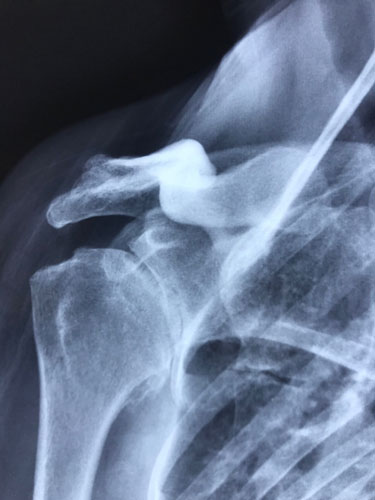

Pre Shoulder Replacement Surgery X-Ray for Arthritis